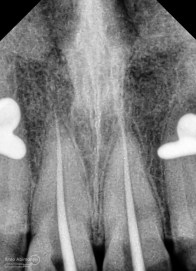

Kemudian dilakukan pengepasan guttap dan difoto ronsen….

Dari ronsen terlihat guttap sudah pas dan langsung hari itu juga saya lakukan pengisian saluran akar kemudia pasien pulang…. Pada saat selesai pengisian tidak saya lakukan ronsen lagi karena saya merencanakan ronsen evaluasi pengisiannya sekalian foto ronsen saat pengepasan guttap pada gigi 22 saja biar efektif…

Prosedur sama seperti kemarin memasangkan rubber dam dahulu untuk isolasi daerah kerja, kemudian melakukan akses ke kamar pulpa… Penjajakan awal saluran akar menggunakan K-file nomer 10, dan panjang kerja diukur menggunakan apex locator… Irigasi dan aktivasi masih menggunakan metode yang sama juga… Setelah prosedur cleaning and shaping selesai dilakukan pengepasan guttap dan difoto ronsen…

Nah dari foto ronsen ini juga saya melakukan evaluasi hasil pengisian pada gigi 11 21 nya… alhamdulillah pengisian yang kemarin terlihat sepanjang kerja dan padat serta rapat… Pada gigi 22 nya pun pengepasan guttap terlihat sudah sepanjang kerja…

Pengisian dilakukan hari itu juga, kembali dilakukan foto ronsen setelahnya..